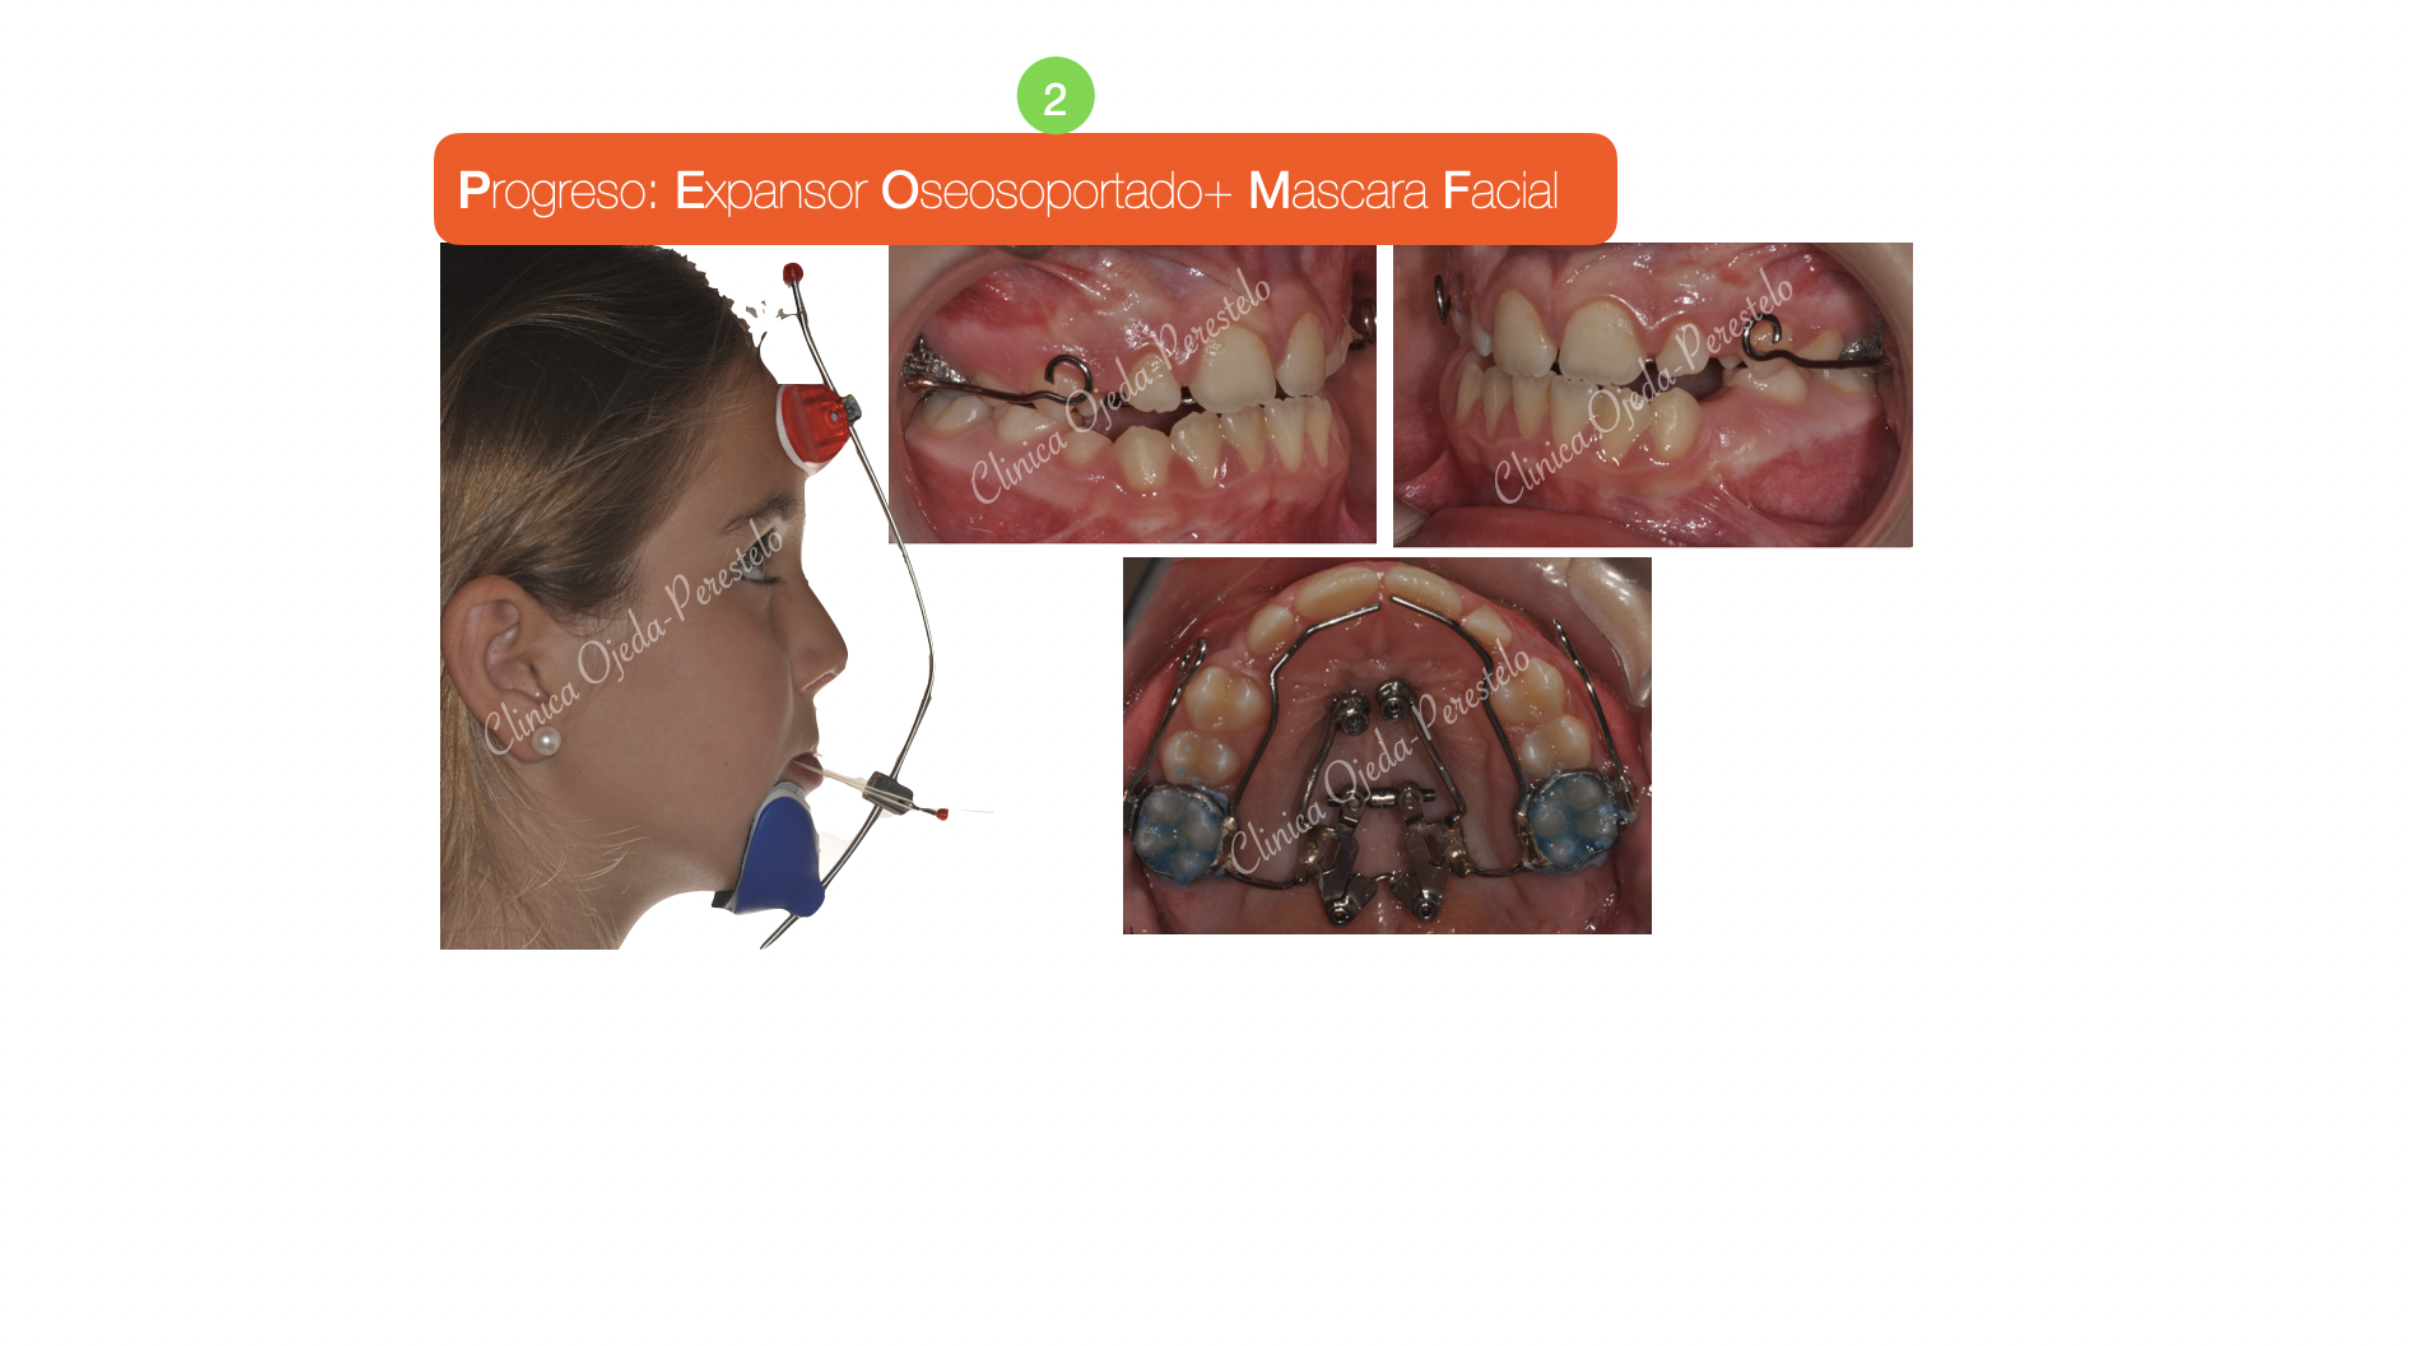

Paciente niña en dentición mixta y clase III esquelética tratado con Ortopedia Maxilar.

Se decidió combinar un Disyuntor Oseosoportado con una Máscara Facial ya que presentaba un déficit esquelético del Maxilar. El impacto facial alcanzado con esta estrategia ha sido relevante y equivalente al que observamos en una intervención quirúrgica del Maxilar (Cirugía ortognática Unimaxilar).